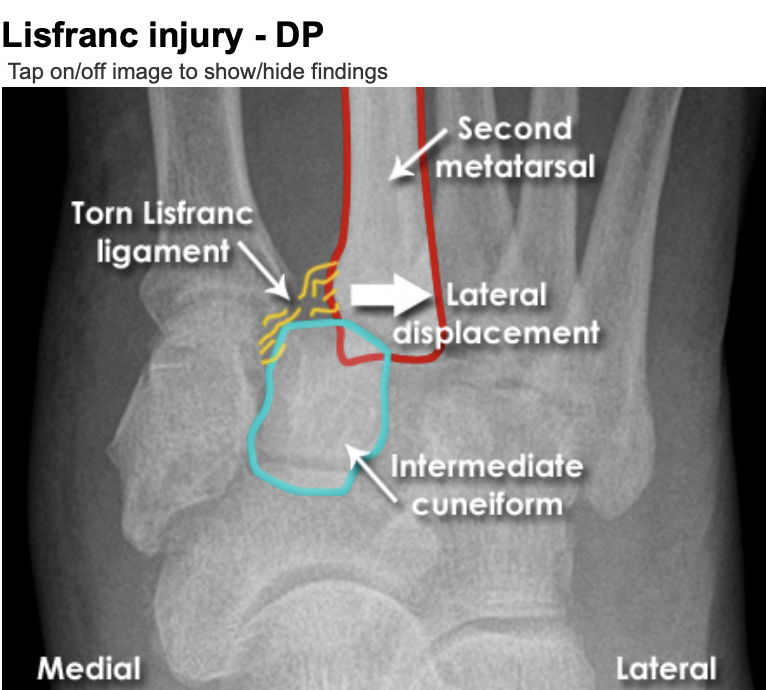

A

A Lisfranc injury is a tarsometatarsal fracture dislocation characterized by traumatic disruption between the articulation of the medial cuneiform and base of the second metatarsal.

* Diagnosis is confirmed by radiographs which may show widening of the interval between the 1st and 2nd ray.

**Lisfranc Injury**